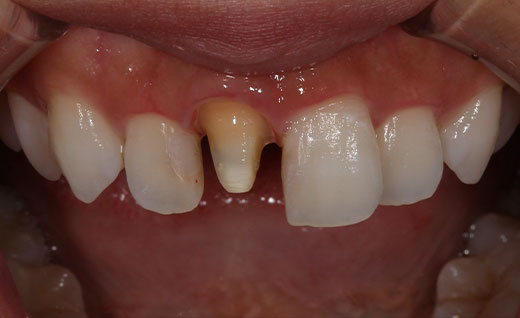

施術中

オールセラミックの土台を形成していきます。